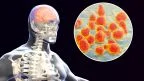

Hantavirus: cos'è, come si trasmette e come proteggersi Cos'è l'hantavirus, come si trasmette e quali sono i sintomi. Tutto quello che devi sapere sul focolaio 2026 e come proteggerti dai rischi dei roditori. 08.05.2026

Hantavirus: cos'è, come si trasmette e come proteggersi Cos'è l'hantavirus, come si trasmette e quali sono i sintomi. Tutto quello che devi sapere sul focolaio 2026 e come proteggerti dai rischi dei roditori. 08.05.2026